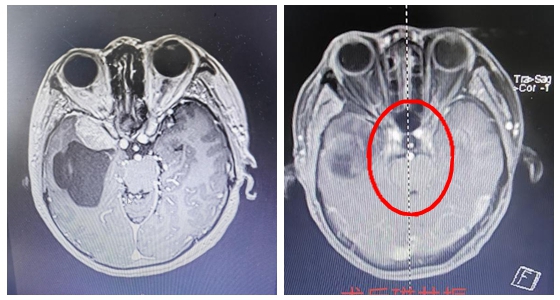

今年72岁的宋奶奶于半年前无明显诱因下出现左侧耳鸣伴听力减退,当时未予重视,3周前耳鸣加重,在当地通过头颅MRI检查,竟然发现了宋奶奶颅内左侧桥小脑角区见一团块状占位性病变,约...